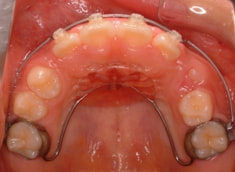

治療法:上顎拡大装置+フルパッシブブラケット(クリアスナップ)+フェイスマスク等

治療前